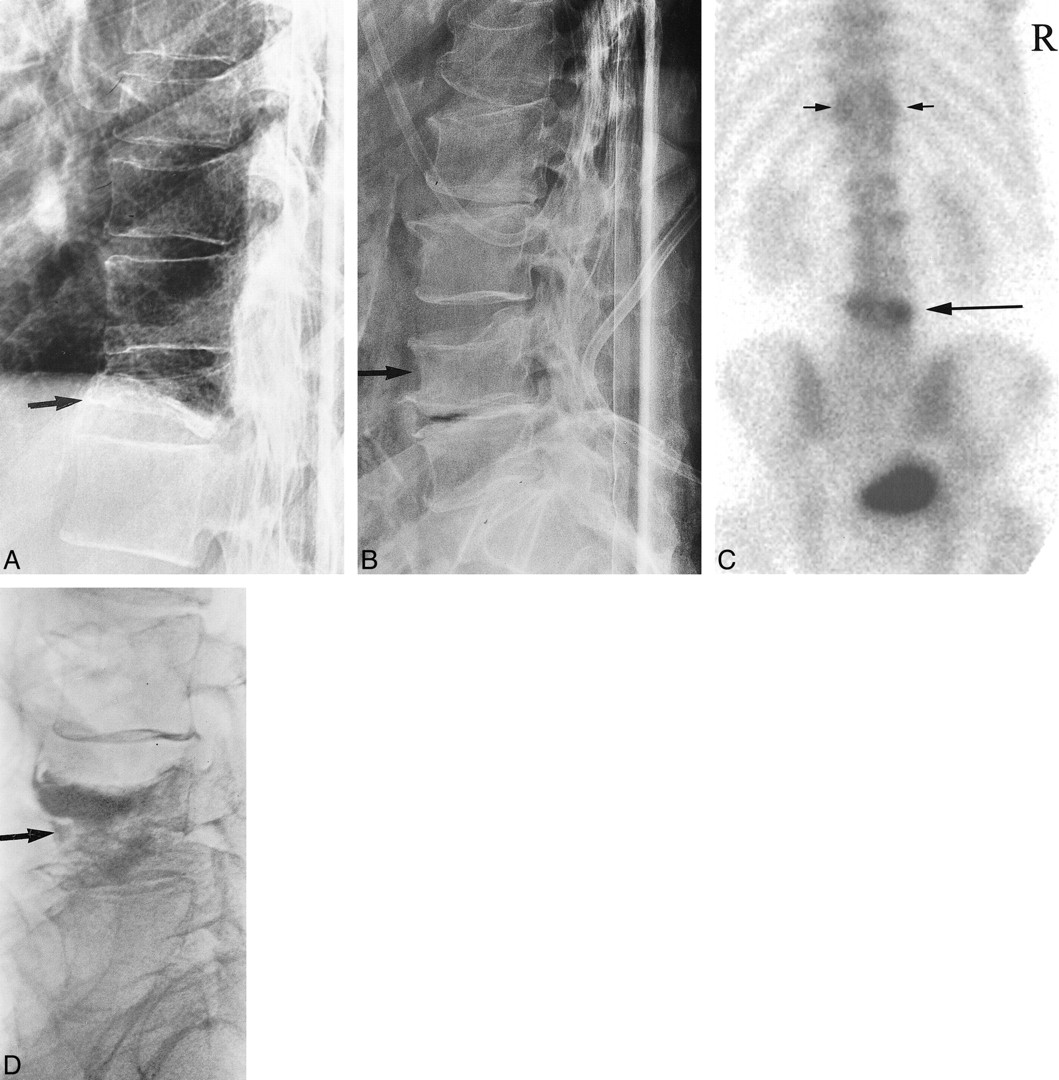

Images from the case of a 79-year-old man who presented with a history of back pain of several months' duration. Although the patient complained of mid and low back pain, he did not experience localizing pain during physical examination.

A, Lateral view plain film radiograph of the thoracic spine shows wedge compression fracture at T11 (arrow).

B, Lateral view plain film radiograph of the lumbar spine shows wedge compression fractures at L4 (arrow) and endplate compression fractures of L1, L2, and L3.

C, Posterior planar Tc99m-MDP bone scan image shows markedly increased activity at L4 (large arrow) and minimal increased activity over the pedicles or facets of T11 (small arrows). Based on increased activity over L4 and relative lack of increased activity at other fracture sites, we proceeded with a single-level vertebroplasty at L4.

D, Lateral view plain film radiograph of the lumbar spine after vertebroplasty shows barium-opacified methylmethacrylate within the L4 vertebral body (arrow). The patient experienced complete pain relief after treatment. Before treatment, the patient's mobility was limited to walking with assistance. After treatment, he was able to walk without assistance.